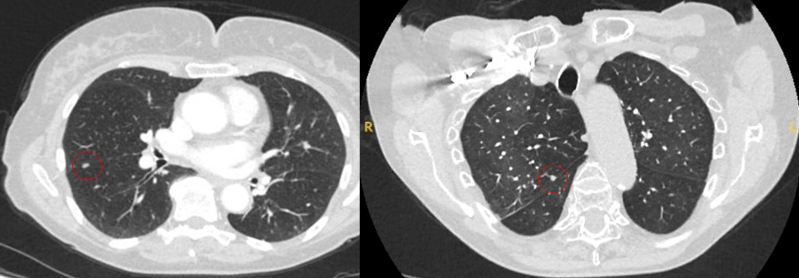

Tomografia computadorizada (TC) mostrando um pequeno nódulo no lobo superior esquerdo com margens lisas, posteriormente considerado uma metástase colorretal solitária na ressecção

Tomografia computadorizada (TC) mostrando duas áreas (círculos vermelhos) de impactação mucoide dos brônquios subsegmentares do lobo superior esquerdo, resultando em aparência que mimetiza um nódulo

Do acervo de Dr. George Tsaknis, MD, PhD, FRCP (Londres), MRQA, MAcadMEd, PGCert; usado com permissão